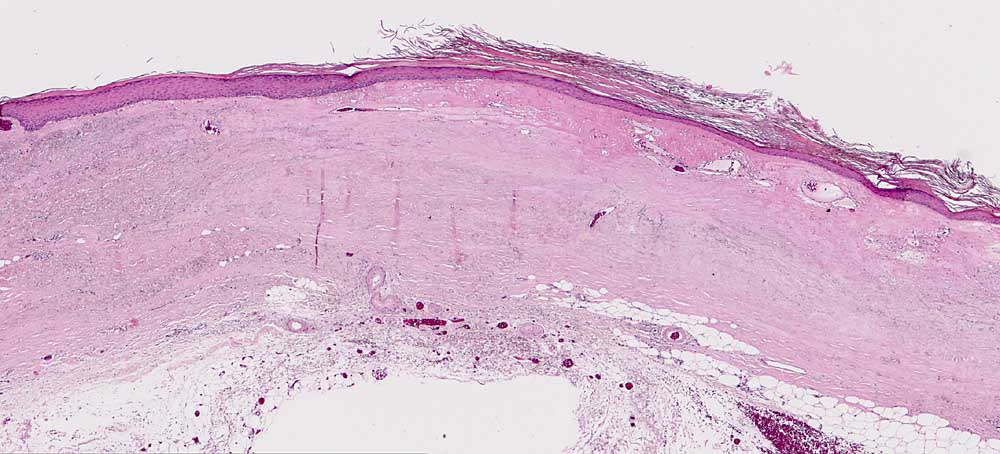

Chronische Radiodermatitis

Therapiefolgen

Haut

Haut, Rumpf

Pathologischer Befund